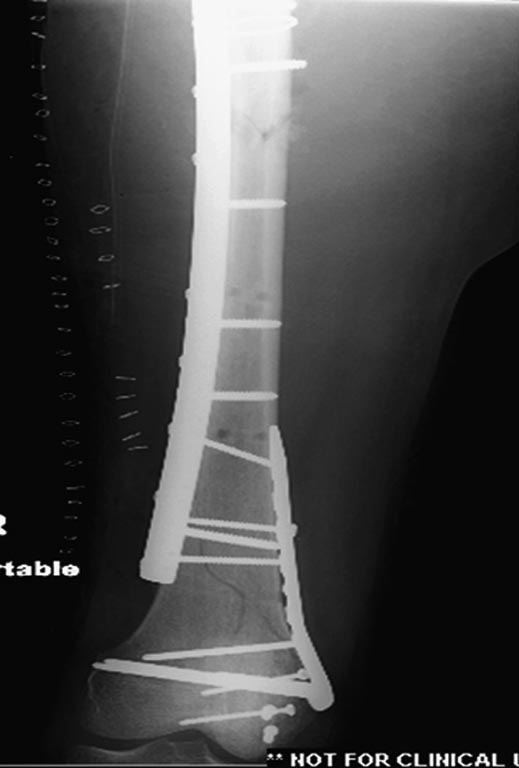

На 25 день с момента травмы операция на Jackson table с боковым обширным

доступом. Удаление стержней с местной обработкой. В тазобедренном

суставе удаление головки, на дне вертлужной впадины полная отслойка

хряща. Вертлужный компонент с одним винтом и короткая ножка -  Fitmore

press fit stem. На второй день однократно доза радиации для профилактики

гетеретопической оссификации.  Послеоперационный период без температуры.

Выписана. Нагрузку разрешили на левой стороне, а полная в 3 мес.  Здесь

снимки при амбулаторном наблюдении​: послеоперационно, 2 мес, 3 мес и 6

мес. Нагрузка полная, отсутствует хромота, и нет жалоб.